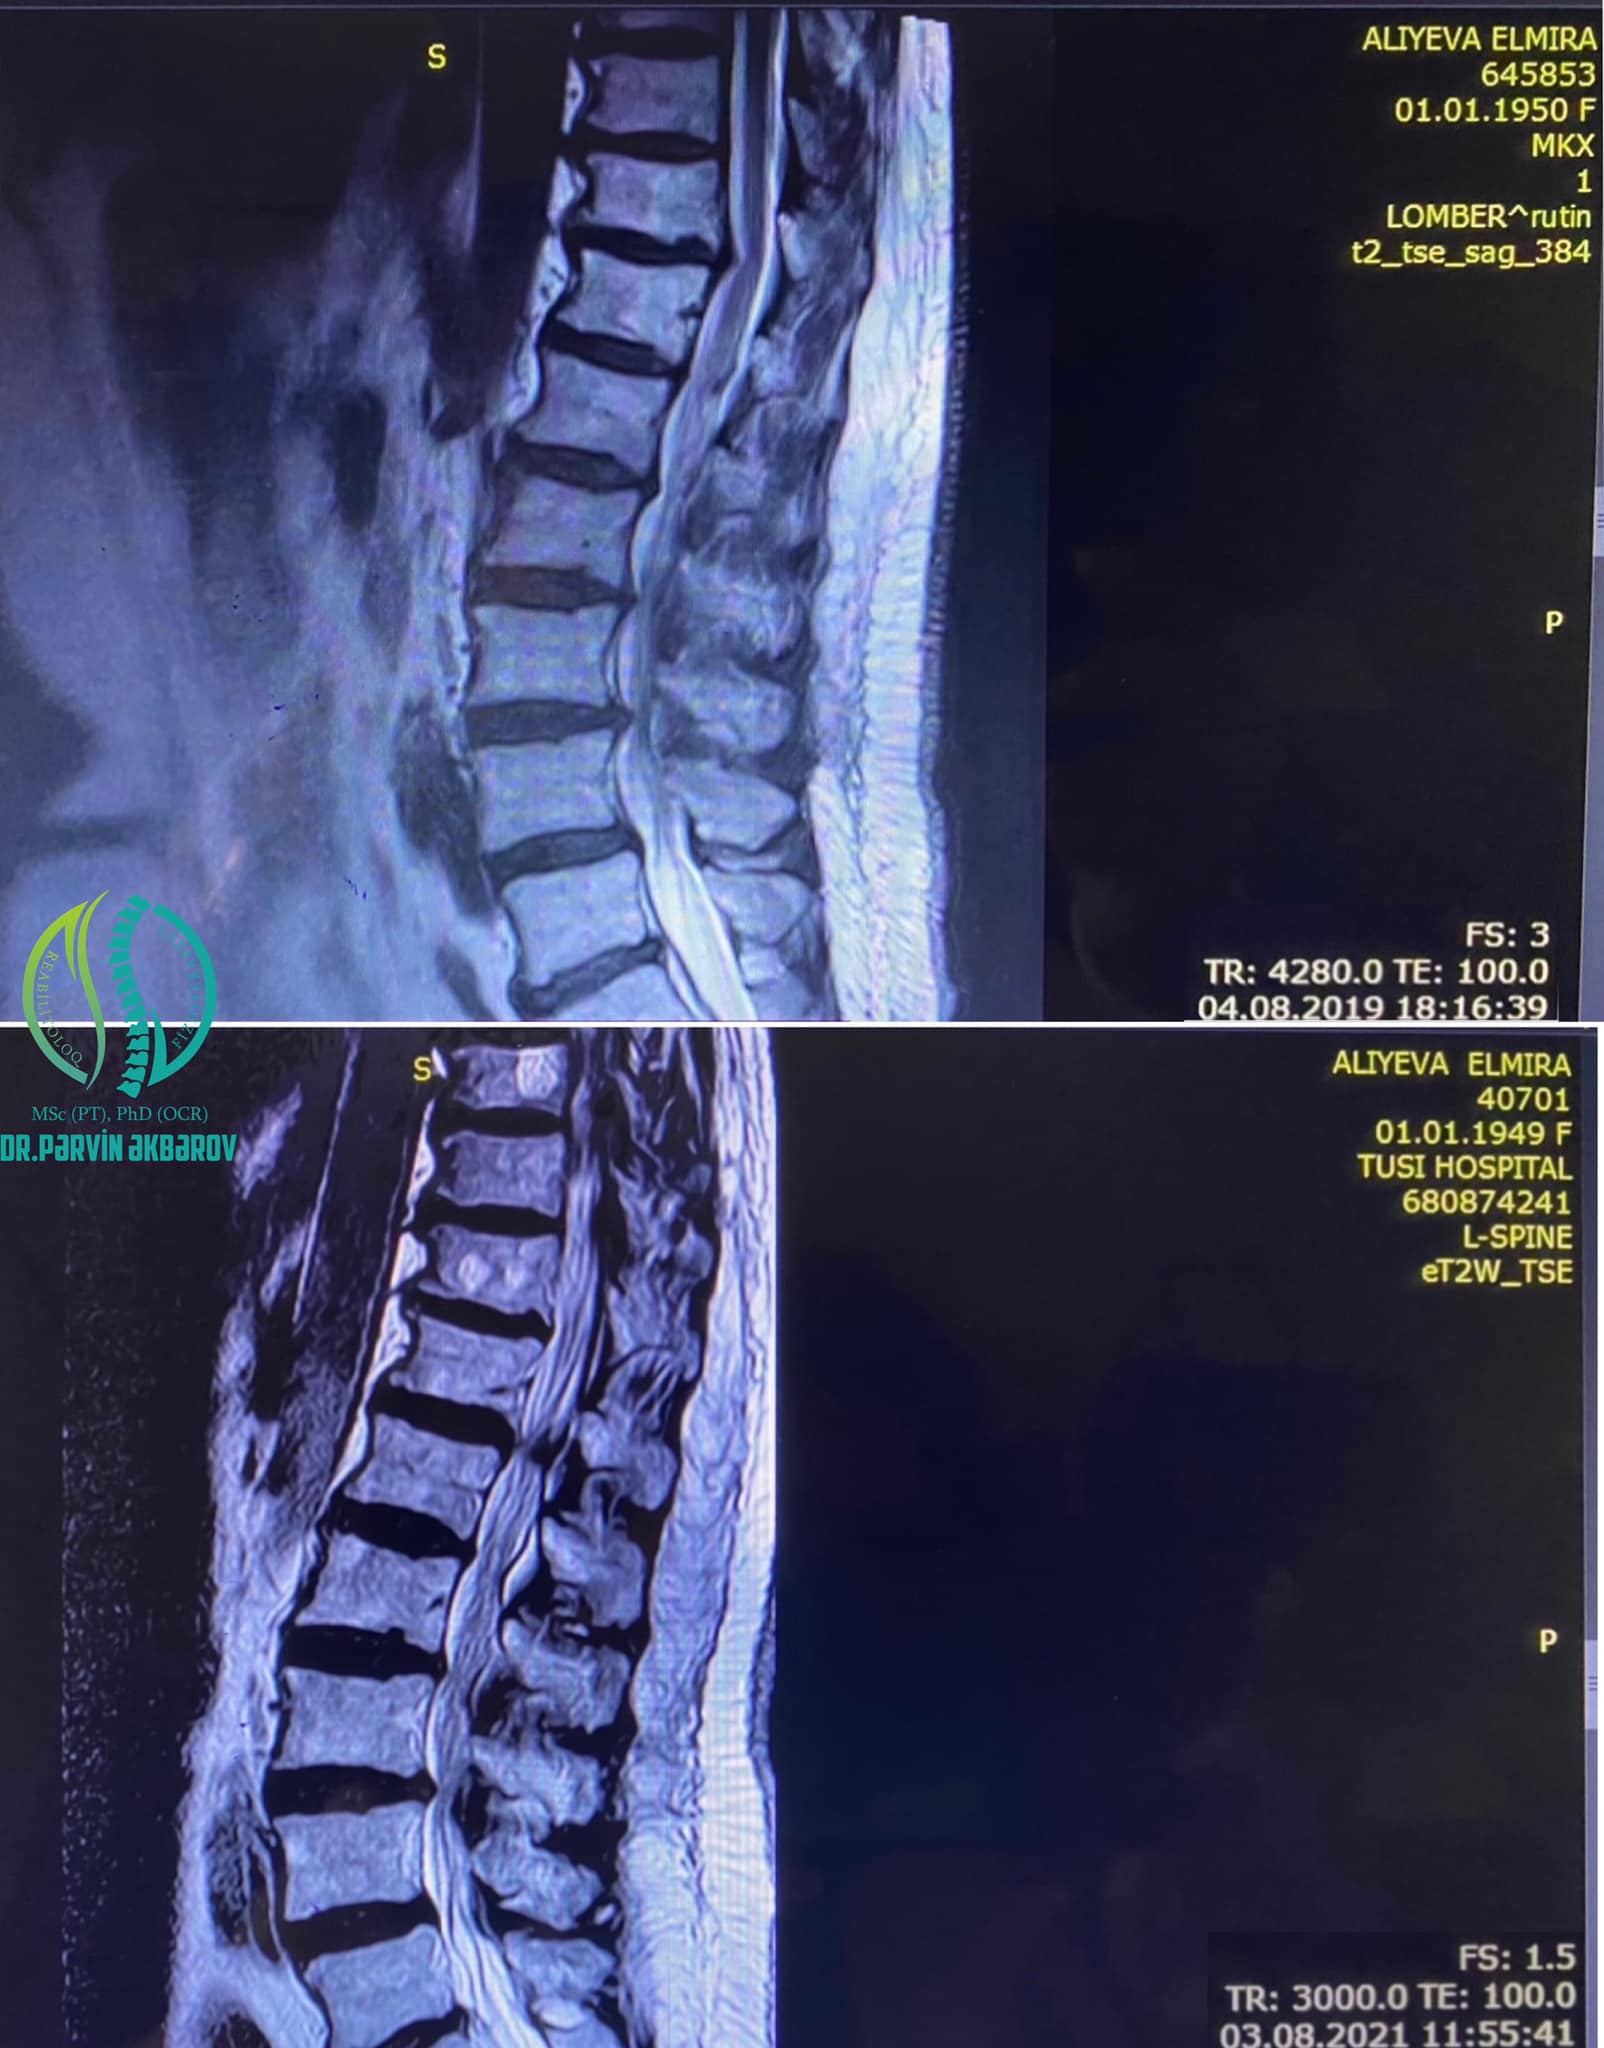

Həkim bildirib ki, gərgin iş qrafiki, saatlarca davam edən əməliyyatlarda uzun müddət ayaqüstə qalmaq məcburiyyətində olan həkimin MRT müayinəsində sekvestrasiyaya uğramış, najot sinirini sıxan 15 mm ölçüdə disk yırtığı aşkar edilmişdir:

"Birbaşa əməliyyata göstəriş olsa da, Elmira xanım cərrahi üsula üz tutmadan öncə konservativ - dekompression müalicəni sınamaq üçün bizə müraciət etdi. Müalicə nəticəsində disk yırtığı 15 mm-dən 5 mm-ə kimi kiçildi, həkimimiz cərrahi əməliyyat riskindən azad oldu".